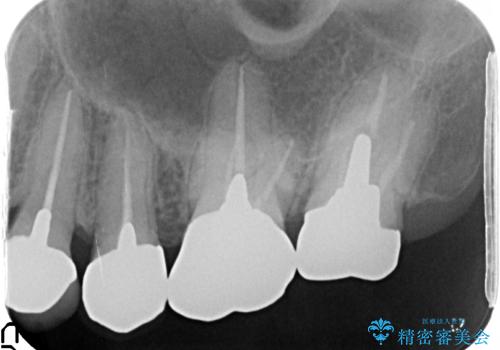

X線写真・視診より歯の破折クラウン下の虫歯再発が認められます。

クラウンの除去・虫歯の除去、根管治療を行ったのち、上顎は強い咬合力に対し破折抵抗性のある咬合面をメタルにしたメタルボンドによる補綴を計画します。